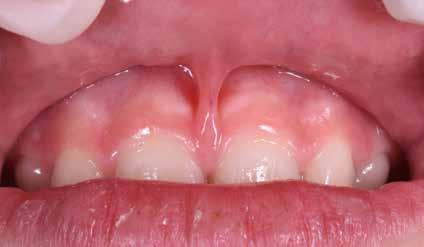

Frenuli delle Labbra

Nell’età della dentizione mista, di tutti i frenuli risulta importante soprattutto quello del labbro superiore (vedi capitolo 10). Il forte sviluppo di tale frenulo può causare la formazione di un distema mediale (Olivi et al. 2010). Per quanto concerne la diagnosi differenziale, la frenulectomia risulta indicata soltanto qualora il frenulo labiale presenti un’inserzione molto bassa e si fonda, sul lato palatale, con la papilla incisiva. Sotto il proflo radiologico, tra le radici degli incisivi superiori si osserva un’incisura che indica il passaggio interosseo delle fbre. La frenulectomia dovrebbe comunque venire effettuata solamente dopo l’eruzione degli incisivi laterali superiori Figg. 17-18

Non è sempre possibile sottoporre il paziente a queste indagini diagnostiche; per migliorare il successo e la riuscita del protocollo è necessario un approccio meticoloso ed una serie di informazioni e un’analisi dettagliata dei comportamenti per rendere il paziente collaborante, come descritto precedentemente. Questo tipo di documentazione non prevede radiografe vista la giovane età del paziente e, quindi, la diagnosi dovrà basarsi sull’esame clinico, fotografco e sull’anamnesi familiare (Snow 2005) Figg. 22-46